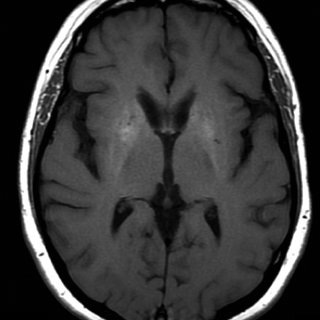

Астроциты оказались ключевыми участниками формирования страха — это может изменить подход к лечению ПТСР

Долгое время астроциты считались в основном «вспомогательными» клетками мозга — чем-то вроде обслуживающего персонала для нейронов. Но новая работа показывает, что их роль заметно глубже. Исследователи из Университета Аризоны (University of Arizona) выяснили, что астроциты в миндалине напрямую участвуют в формировании, поддержании и угасании страха. Это открытие может повлиять на понимание посттравматического стрессового расстройства, тревожных расстройств и фобий. Работа опубликована в журнале «Nature». Авторы сосредоточились на миндалине — области мозга, которая играет центральную роль в обработке страха и эмоционально значимых воспоминаний. Чтобы проследить, как астроциты ведут себя во время обучения страху и последующего угасания этой реакции, исследователи использовали мышиную модель, флуоресцентные сенсоры и методы точечного вмешательства в сигнальные пути астроцитов. Это позволило наблюдать не только активность самих клеток, но и то, как изменение их работы отражается на нейрона